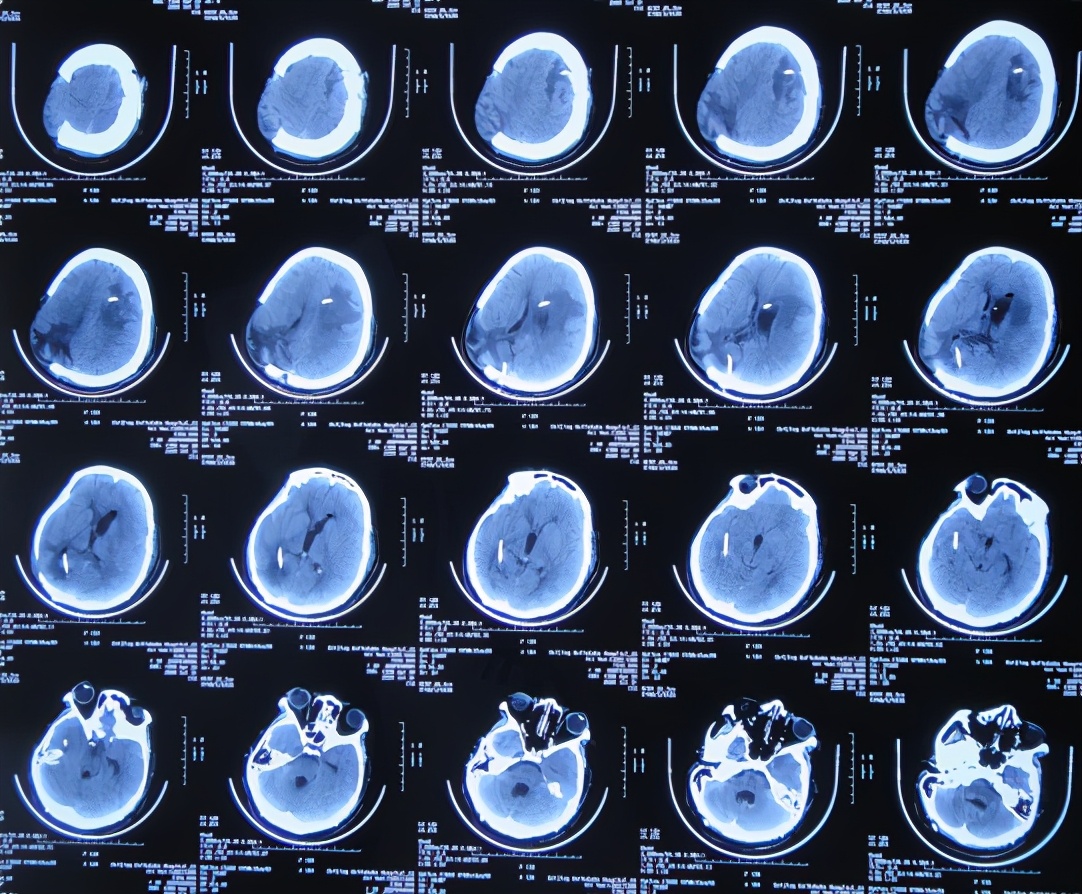

开颅术后15天即2020年4月17日(腰大池引流术后7天),查头颅CT示仍脑膨出( 图-4 ),因腰大池引流管堵塞,给予拔除并第2次重新置换腰大池。

图-4: 2020年4月17日头颅CT